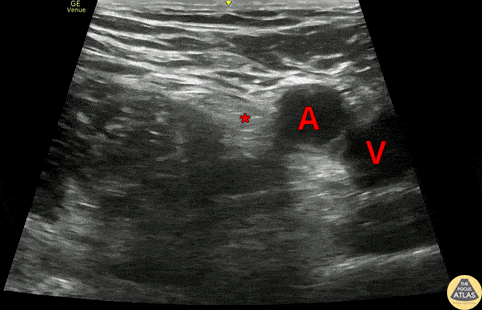

A 60s M presented with hip pain after a fall while skiing. He had a visible closed leg deformity but was neurovascularly intact. Radiographs confirmed a femoral neck fracture. A fascia iliaca compartment block was performed for analgesia and to facilitate orthopedic evaluation. The first part of this clip shows the anatomy of the fascia iliaca, with the femoral artery (A), femoral vein (V), and femoral nerve (*) superficial and medial to the iliacus muscle (I). The fascia iliaca (^) overlies the iliacus muscle. The later portion of the clip shows a fascia iliaca compartment block performed by inserting a needle from the lateral aspect until the tip is just deep to the fascia iliaca, and instilling a large amount (30-40cc) of anechoic local anesthetic in the fascial plane just superficial to the iliacus muscle (I). The injection of anesthetic in this fascial plane allows the anesthetic to spread over a larger anatomic area, providing anesthesia to the lateral femoral cutaneous nerve and obturator nerve in addition to the femoral nerve. Dr. Larry Benjey, PGY3 Denver Health Residency in Emergency Medicine